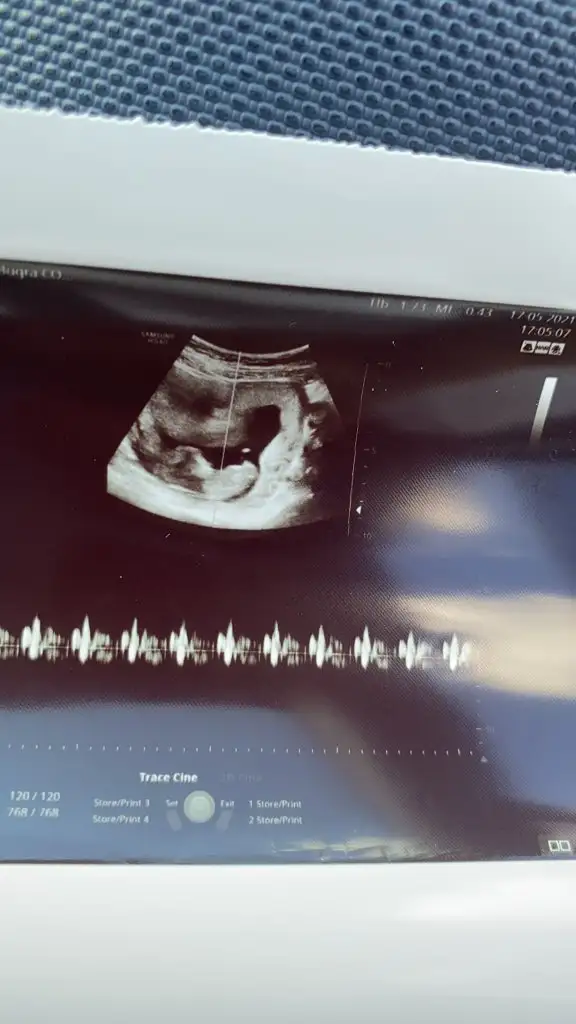

Ikra meyra Ikra meyra merhabaaa Canım :) Arkadaşımın bebisinin fotosunu atiyorum.Sana zahmet tahminde bulunabilirsen çoooook sevinirim :) Şu an 12+2 :)

Eklentiler

• IMG-20210517-WA0002.webp

IMG-20210517-WA0002.webp

27,3 KB · Görüntüleme: 66

• IMG-20210517-WA0001.webp

IMG-20210517-WA0001.webp

12,3 KB · Görüntüleme: 61

• IMG-20210517-WA0000.webp

IMG-20210517-WA0000.webp

13,7 KB · Görüntüleme: 64